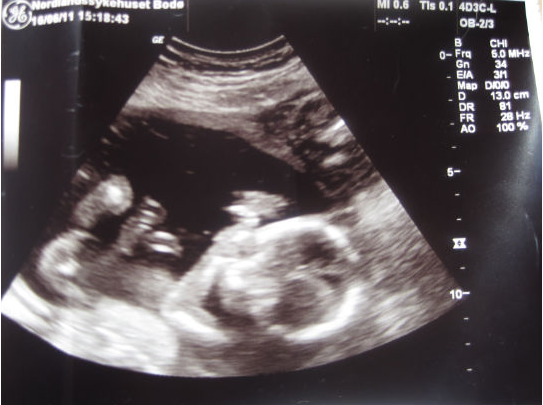

Teriyaki Skrevet 20. juni 2011 Forfatter #828 Skrevet 20. juni 2011 (endret) Jeg har hatt nesten flat mage begge svangerskap frem til uke 21-22, deretter har den poppet. Greit med nytt nick innimellom, har skiftet et par ganger jeg også Ja den kommer vel etter hvert! Snikleser melder seg. Nå vil jeg ha deg på mine innlegg. Gratulerer med gutt! hit! Alltid artig med sniklesere som melder seg Tusen takk for det! Har lagt inn bildene på pc nå, så tenkte jeg skulle legge ut de to beste. Endret 20. juni 2011 av Teriyaki

Gjest Delphina Skrevet 20. juni 2011 #829 Skrevet 20. juni 2011 Så skjønne bilder. Vi har tre av snuppa, to av dem i uke 13 og en av henne i uke 21. Alle sier hun smiler på uke 21 bildet, men tror hun bare svelget litt fostervann rundt den tiden.

Gjest Krizzy Skrevet 20. juni 2011 #832 Skrevet 20. juni 2011 hit! Alltid artig med sniklesere som melder seg Tusen takk for det! Har lagt inn bildene på pc nå, så tenkte jeg skulle legge ut de to beste. Ja, nå orka jeg ikke drive å finne fram lengre. Mye enklere å ha deg på mine innlegg.... Så nydelig liten gutt!